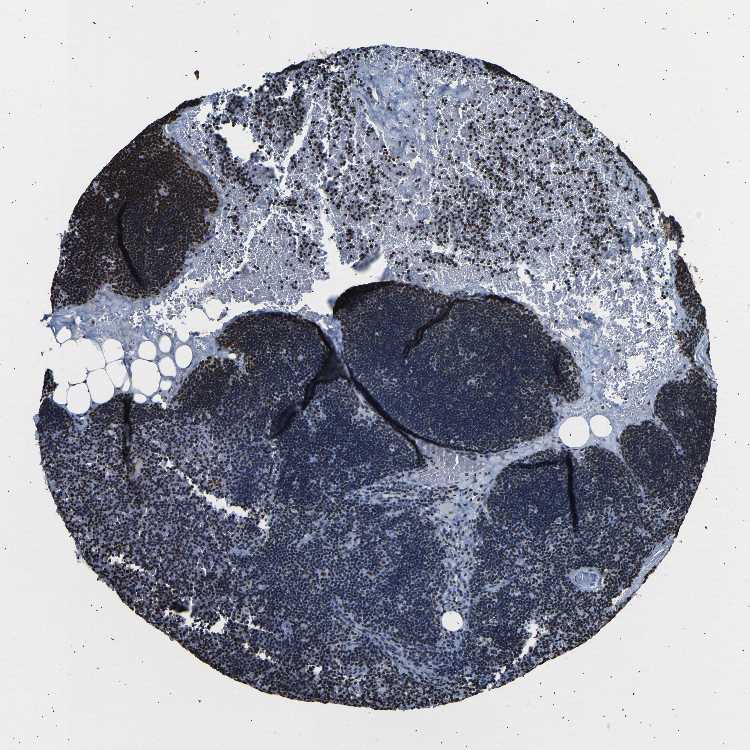

TISSUE PRIMARY DATA LYMPH NODE Show tissue menu

Lymph node

Lymphoid tissue

LYMPH NODE - Expression summary

LYMPH NODE - Antibody stainingi

Antibody staining in the annotated cell types in the current human tissue is reported as not detected, low, medium, or high, based on conventional immunohistochemistry profiling in selected tissues. This score is based on the combination of the staining intensity and fraction of stained cells.

Each image is clickable and will lead to virtual microscopy that enables deeper exploration of all samples and also displays staining intensity scores, fraction scores and subcellular localization as well as patient and tissue information for each sample.

Antibody HPA061301Antibody CAB013073

Germinal center cells HighHigh

Non-germinal center cells HighHigh